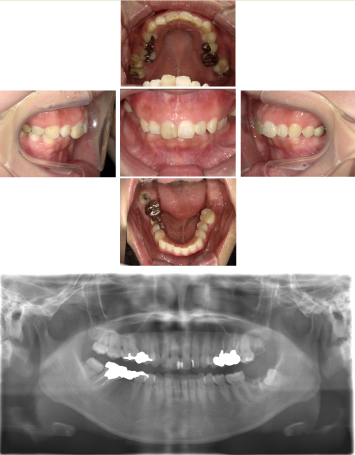

30代 女性 奥歯 インプラントGBR

| 年代・性別 | 30代・女性 |

| 治療回数 | 1回 ※術前治療・検査除く |

| 治療期間 | 5ヶ月 |

| 料金 | ¥60,000(税込) |

GBR(Guided Bone Regeneration:骨再生誘導法)とは、インプラント治療において、骨の厚みや高さが足りない場合に行う歯槽骨を再生する方法です。骨量不足の患者様でも、骨造成を行うことでインプラントの埋入に必要な骨の高さや厚みが得られます。 GBR(再生誘導法)は、骨が痩せて十分な骨量が確保できない患者様に、骨の再生によってインプラントの埋入を可能にする治療方法の一つです そのような骨が欠損した部分では、骨を作る「骨芽細胞」よりも、骨にならない「線維芽細胞」の方が増殖しやすいという特徴があります。そのためGBRでは、骨形成の妨げになる繊維芽細胞の侵入を防ぐため、骨を増やしたい部分を「メンブレン」という人工膜で覆い、その中に自家骨や人工の骨補填材を詰めて骨芽細胞の増殖を促します。 |

| 副作用 | 術後に腫れ・痛みが出る可能性がある。 |